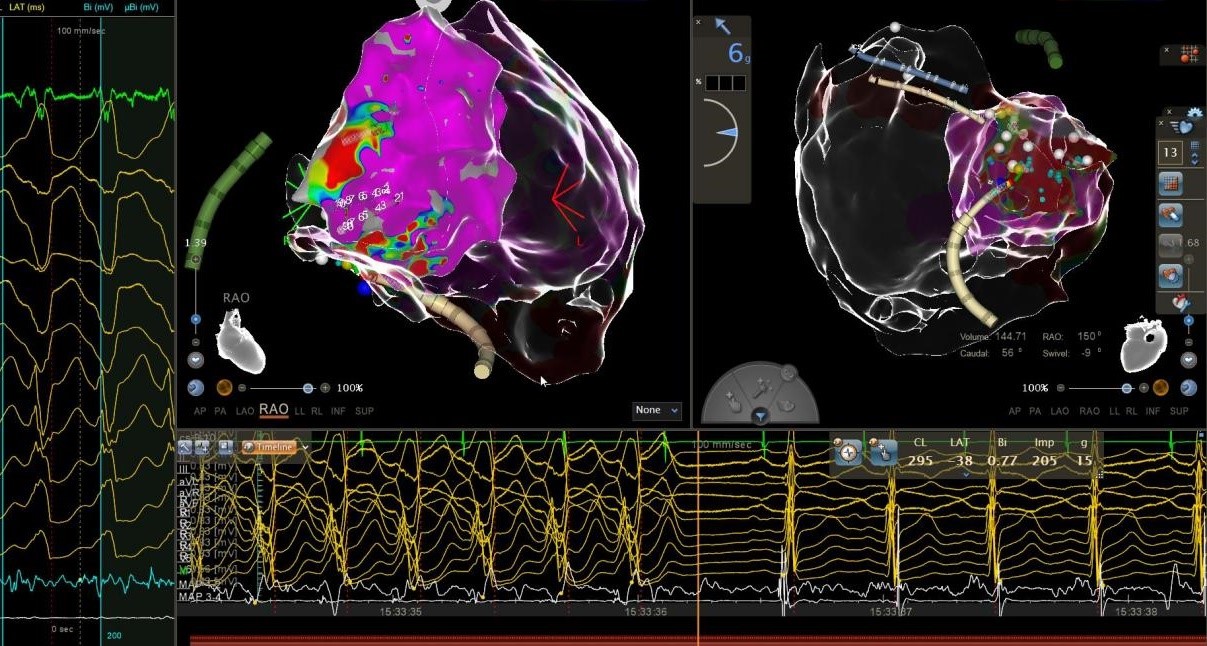

面对这一挑战,在学科带头人周亚峰教授的指导下,陈弹主任医师、王林林教授带领心内科电生理团队共同制定了三维电解剖标测联合心内外膜基质改良的手术方案。手术由王林林教授主导进行,术中通过双侧股静脉入路,精准构建右心室三维模型,标测出右心室下壁广泛低电压区。团队突破性采用干性心包穿刺技术,成功进入心外膜空间,术中采用高功率盐水灌注消融,消融后室速实时终止,并对心内膜、心外膜低电压区进行基质改良。经反复程序刺激验证,室速不再被诱发。术后患者恢复良好,未再出现室速发作,心悸症状完全缓解。相较于传统ICD植入的被动防御,射频消融术通过主动消除心律失常基质,显著降低年轻患者的猝死风险及器械依赖,为其重返正常生活提供可能。